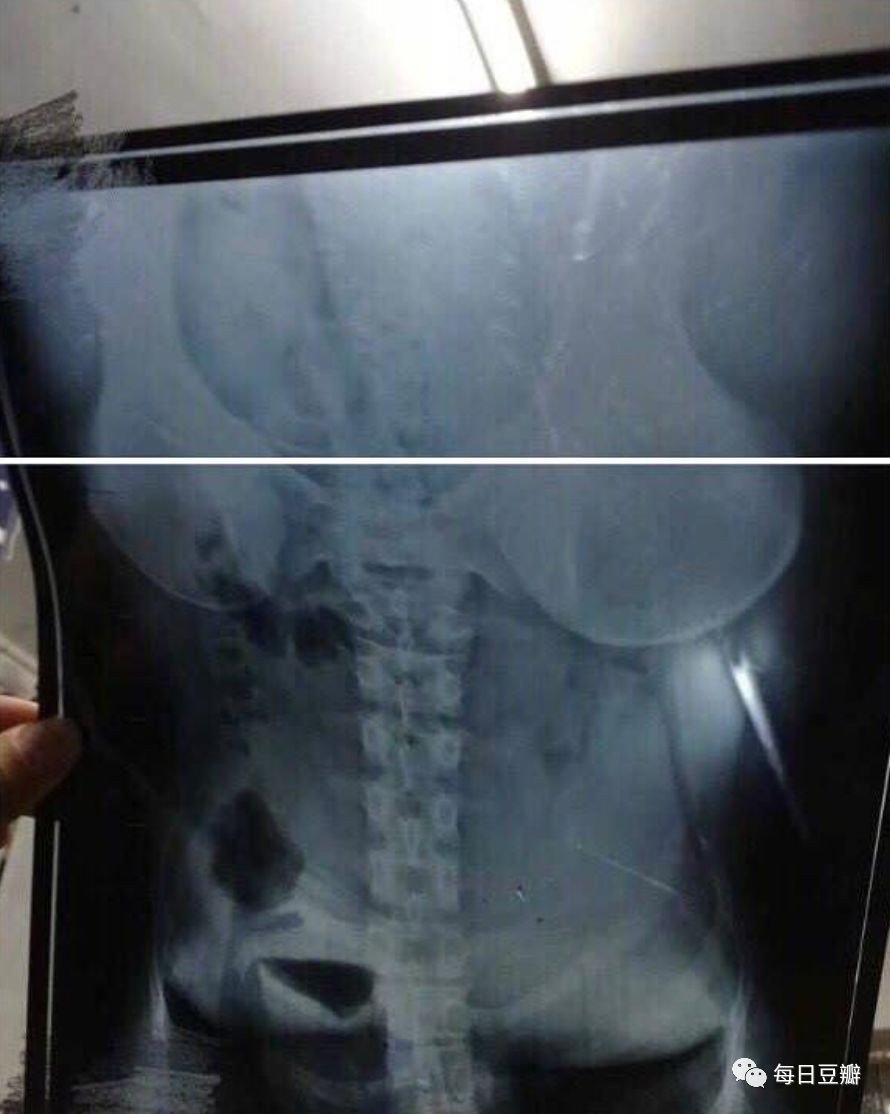

某天上午我在寝室打扫卫生,看到地上有一张光片,我就捡起来了,顺便扫了一眼,顿觉惊呆:

我怎么记得高中物理有讲

x光片能拍骨头,怎么现在连背心也能拍出来???

带着疑问的我,等到了晚上

一票室友差不多都回来了,我便拿出这个片子提问:这个是谁的片子呀?

众人观望,都说不是自己的

哦,那就是小八的了

我也没想太多,顺带提出了我内心的疑问:为什么拍片可以把背心拍出来?

众人惊,纷纷相望

老三:“怎么看着像mm??”

老二:“那是胸罩吧”

老大:“不对,应该是背心,肩带是宽的”

我和老大确认了眼神

果然,英雄所见略同

不大一会

小八回来了。

我:小八,这是你的片子吧。现在技术竟然能把背心拍出来,真·不可思议

小八:???

我:你看,这是背心吧,肩带是宽的

小八:· _ ·?不是这个角度,这是拍的肚子,你拿反了

你拿反了

拿反了

反了

...

正确姿势如下图